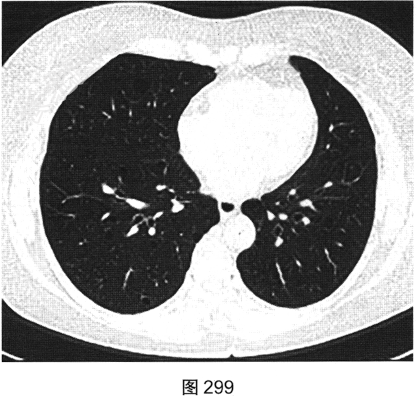

- 多项选择题3.[提示]HRCT图像如图298~图301所示。从患者的HRCT图像中可见哪些阳性征象( )

A、双侧腋窝及纵隔内多发增大淋巴结

B、双肺多发薄壁透亮影

C、小叶间隔增厚

D、右肺多发钙化结节灶

E、双肺多发磨玻璃样密度影

F、支气管扩张